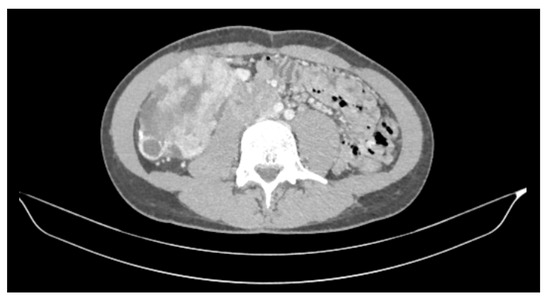

2. Case Report